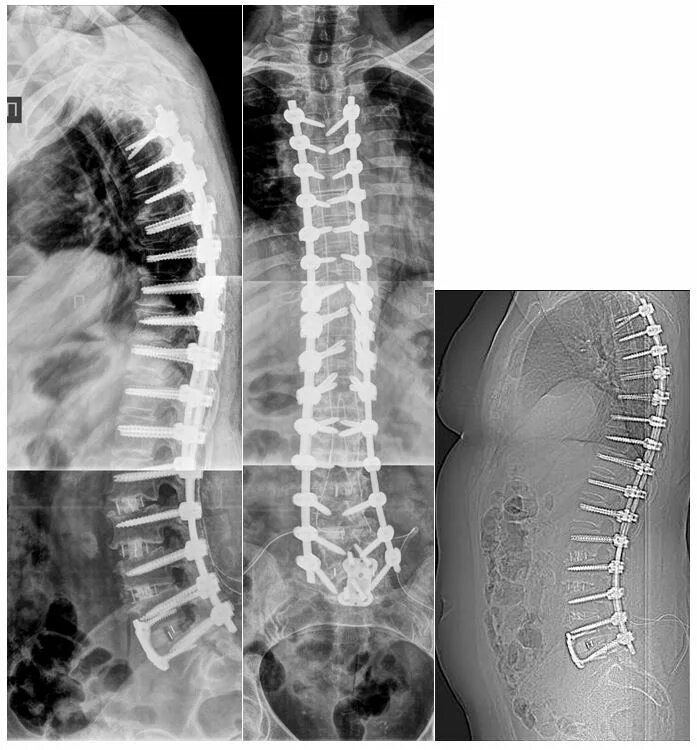

Дегенеративные изменения крестцового отдела